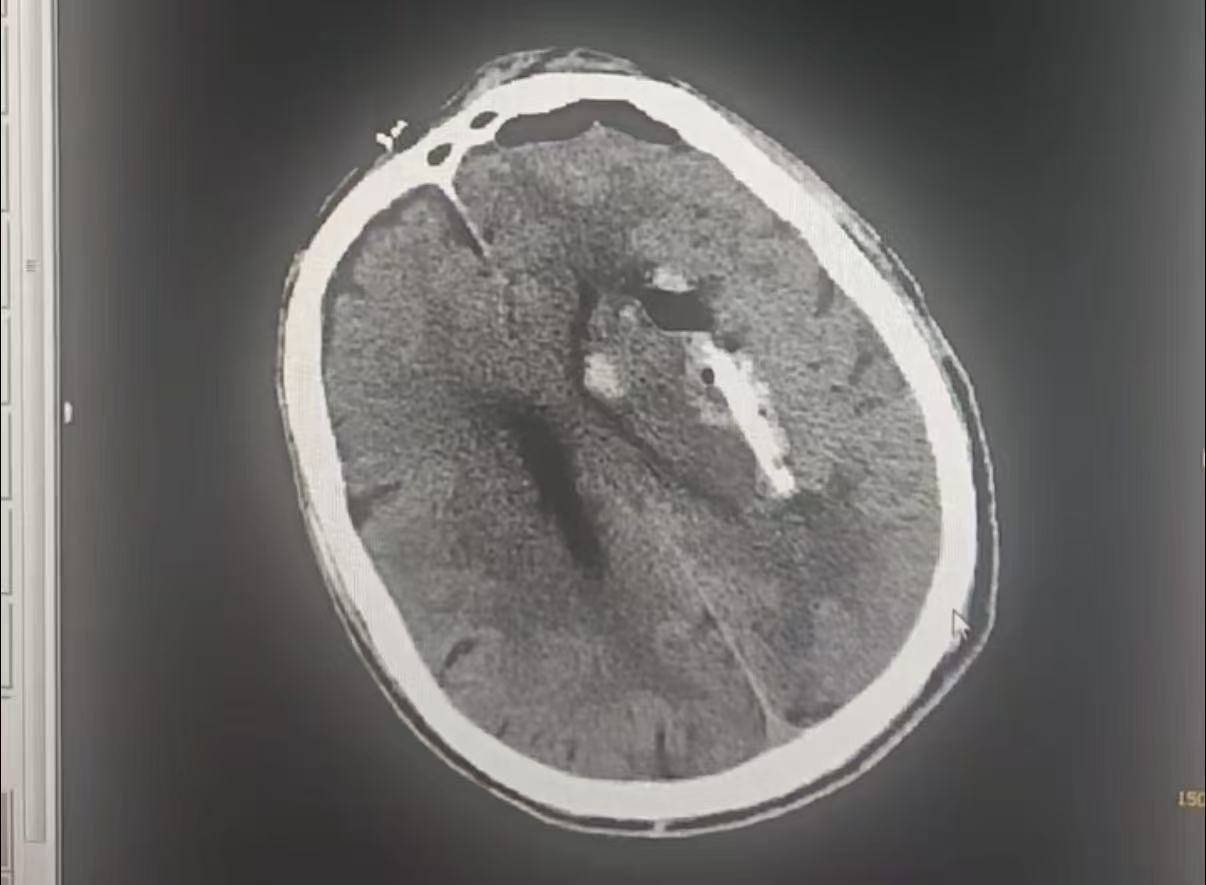

据悉,该患者为老年男性,因颅内血肿就诊,病情危急且基础情况复杂。考虑到患者年龄大、基础疾病较多,无法耐受传统开颅手术的创伤,科室团队经过缜密评估,决定采用3D打印微创穿刺抽吸血肿技术,为患者制定个性化诊疗方案。

手术过程精准高效,凭借3D打印技术对血肿位置、形态的精准定位,穿刺路径规划科学合理,有效减少了手术创伤,整个手术时长大幅缩短,最大程度降低了手术风险。

(术前)

(术后)